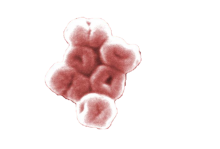

Acinetobacter [asz−in−ée−toe–back−ter] is a group of Gram-negative bacteria commonly found in soil and water. While there are many types or “species” of Acinetobacter, and all can cause human disease, Acinetobacter baumannii [boe-maa-nee-ie] accounts for about 80% of reported infections. Outbreaks of Acinetobacter infections typically occur in intensive care units and healthcare settings housing very ill patients. Acinetobacter infections rarely occur outside of healthcare settings. Significant outbreaks with this pathogen were tied to soldiers injured during the Iraq war.